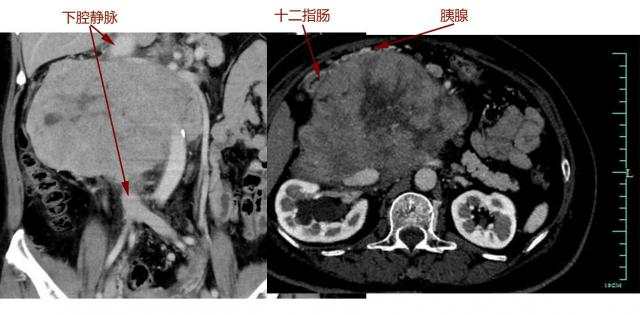

很快,吴女士转院至浙大一院肿瘤外科,完善各项术前检查后,滕教授发现情况远比最初判断严重:肿瘤与胰十二指肠、肾脏等多个脏器及主干血管关系不清,直接吞噬了腔静脉,双肾血管受累,已有轻度肾功能异常。

"我们做过很多类似的手术,但像她这样与血管黏连这么牢的很少。"滕教授表示,随即组织了放射科、泌尿外科、血管外科、肛肠外科、麻醉科、输血科等进行会诊,制定严密的手术方案。针对术中血管与脏器保留或重建的关键问题,他与肛肠外科主任、小肠移植专家吴国生教授,血管外科主任张鸿坤进行了反复探讨,"肿瘤吞噬了腔静脉,这是人体最重要的血管,就像下水管一样,稍有不慎就会大出血,造成不可挽回的后果,而肿瘤如果侵犯肠系膜,可能还要做自体小肠移植。"

手术过程和预计的一样凶险,手术团队小心翼翼将肠道、肾脏血管从肿瘤成功分离。但真正的困难很快出现:肿瘤与胰腺头部黏连,下腔静脉也被侵犯,滕教授当机立断,切断十二指肠及胰头,游离肿瘤两端下腔静脉,最后分离切除大血管部分肿瘤。由于肿瘤向血管内生长,肿瘤切下的同时血液一涌而出,早有准备的团队立即阻断下腔静脉以控制出血,快速切除肿瘤,张鸿坤主任随即缝合修补下腔静脉。万幸的是,术中发现肿瘤与肠系膜血管黏连不严重,避免了自体小肠移植。